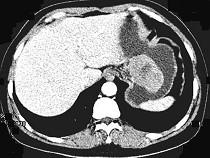

问题 女,51岁,上腹部隐痛不适,CT检查如图,可能的诊断是()

选项 A.胃癌 B.胃息肉 C.胃腺瘤 D.胃溃疡 E.胃间质瘤

答案 E